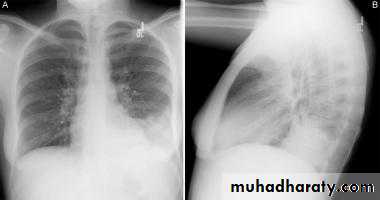

Chest x-rays of a 46-year-old man with SARS. The left lower lung infiltrate seen initially (A) progressed to multiple bilateral opacities (B).

high fever (> 38°C), malaise and muscle aches and later a dry cough with shortness of breath or difficulty in breathing, with history close contact within 10 days of onset of symptoms with a person known to be a suspect SARS case is typical.

The chest X-ray is usually indicative of pneumonia.